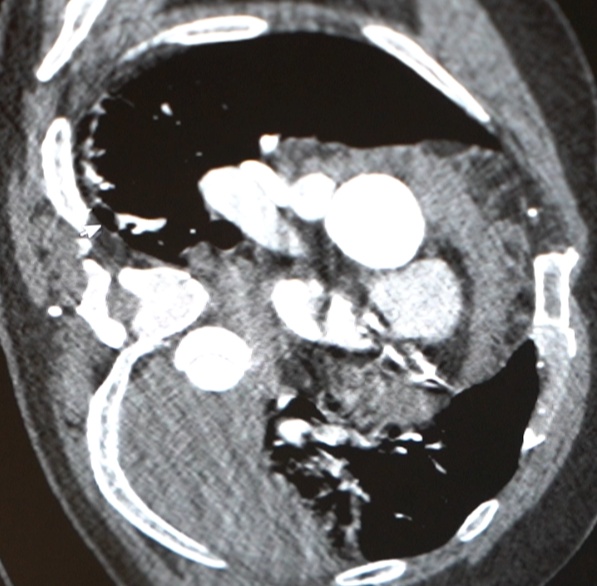

急诊检查结果不容乐观:胸腹主动脉夹层伴胸腔大量积液、纵隔积液——这些积液,考虑是从撕裂的主动脉里漏出来的!

医院心脏血管外科团队紧急会诊,这虽是B型主动脉夹层,但极其凶险,而且他已出现休克表现。“主动脉夹层就像水管壁分层开裂,一旦完全破裂,血液会瞬间涌入胸腔,没有任何抢救机会。他这种情况,已经是命悬一线。”心脏病院副院长张金洲语气凝重。